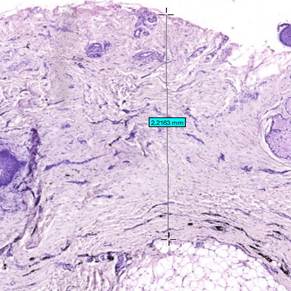

Еще одним числовым показателем, исследуемым на препаратах дермы посттравматических рубцов, была динамика удельной площади участков импрегнации (табл.3). Оценивались наиболее крупные участки импрегнации (рис.5).

Рис.5. Участки импрегнации в дерме рубца до проведения лазерной терапии

Окраска: гематоксилин + эозин; красными стрелками указаны

наиболее крупные участки импрегнации. Ув. х10.

Примечание: составлен авторами по результатам данного исследования

Участки импрегнации были распределены на три группы: крупные, средние и малые. При оценке данного параметра размерности устанавливались относительно полученных данных для каждого препарата индивидуально для нивелирования индивидуальной изменчивости образцов и широких границ вариативности размера частиц пигмента.

Морфометрический анализ показал наибольшее уменьшение количества пигмента в дерме за счет деструкции и элиминации наиболее крупных участков импрегнации. Уменьшение площади крупных участков составило: в паре №1 – 100%; в паре №2 – 72,5%; в паре №3 – 100%. Аналогичная тенденция зафиксирована для средних и малых по площади участков импрегнации.

Площадь средних участков уменьшилась в паре №1 на 100%, в паре №2 – на 80,2%, в паре №3 – на 67,5%. Для малых участков уменьшение площади, занимаемой участками импрегнации, составило: для пары №1 – 39,4%; для пары №2 – 82,8%; для пары №3 – 72,7%. Важно отметить, что в паре №1 терапия привела к полному исчезновению средних и крупных патологических структур, что свидетельствует о высокой эффективности примененного метода воздействия именно на грубые, сформированные дефекты внеклеточного матрикса.

Таким образом, морфометрический анализ препаратов дермы рубцов с импрегнацией однозначно демонстрирует, что высокоинтенсивная лазерная терапия приводит к значительному уменьшению площади и последующему исчезновению участков импрегнации в дерме как посттравматических рубцов, так и рубцов с исходной импрегнацией, что морфологически проявляется в ремоделировании и оптимизации структуры соединительной ткани, что находит свое подтверждение в литературе [14, 15].